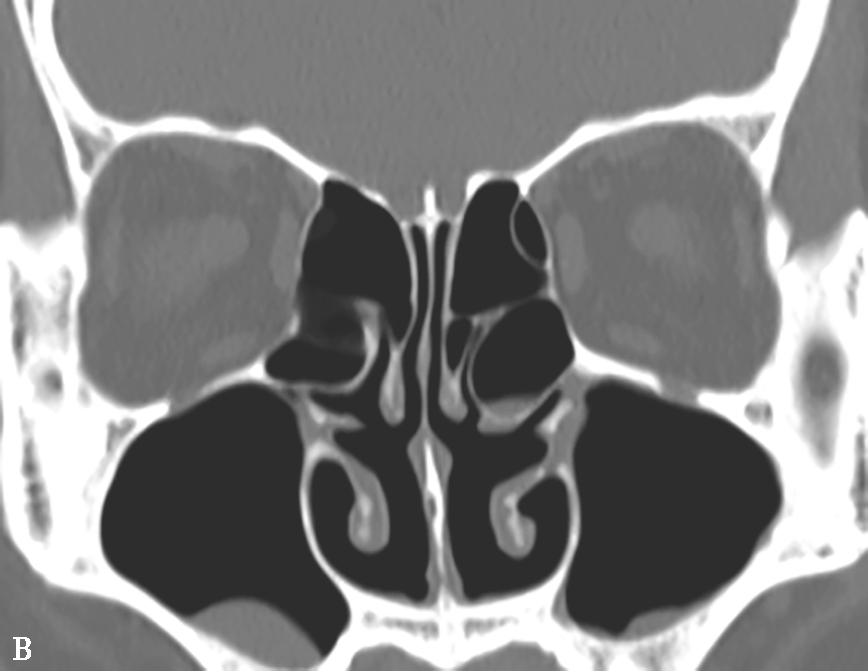

窦口鼻道复合体(ostiomeatal complex,OMC):由于纤维内镜生理性手术的需要,近一二十年来提出了窦口鼻道复合体的概念。窦口鼻道复合体并非一个独立的解剖结构,而是指前组鼻窦自然开口周围的区域,包括中鼻甲、钩突、半月裂、筛漏斗、鼻丘、筛泡、上颌窦自然开口等解剖结构(图1-3-2)。

图1-3-2 窦口鼻道复合体解剖

1.半月裂;2.钩突;3.中鼻道;4.筛大泡;5.筛漏斗;6.上颌窦开口